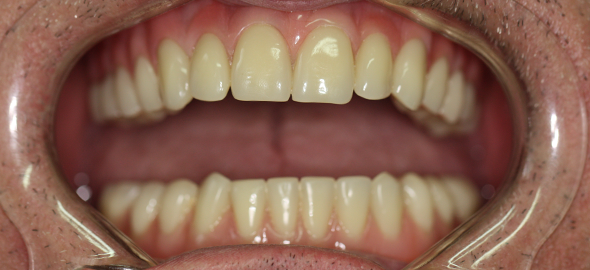

PRÓTESE DENTÁRIA

É a área da odontologia destinada a reposição e reconstrução de dentes naturais, perdidos ou danificados.

É através das próteses que devolvemos ao paciente a função mastigatória, fonética e a estética do sorriso, protegendo a articulação (A.T.M).